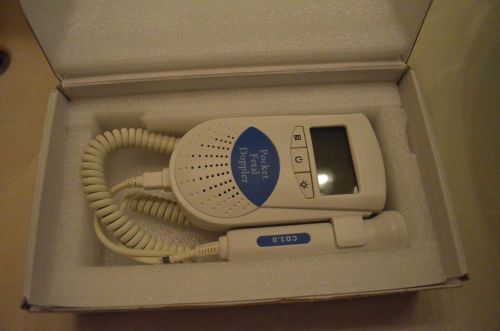

Pocket fetal doppler - Doppler Fetal Monitor - Free shipping

FetalFetal Bond Doppler Heart Beat Monitor Hospital Grade Baby Prenatal

HOT +AAAA Home Use LCD Digital Baby Heart Fetal Doppler Heart Monitor + GEL